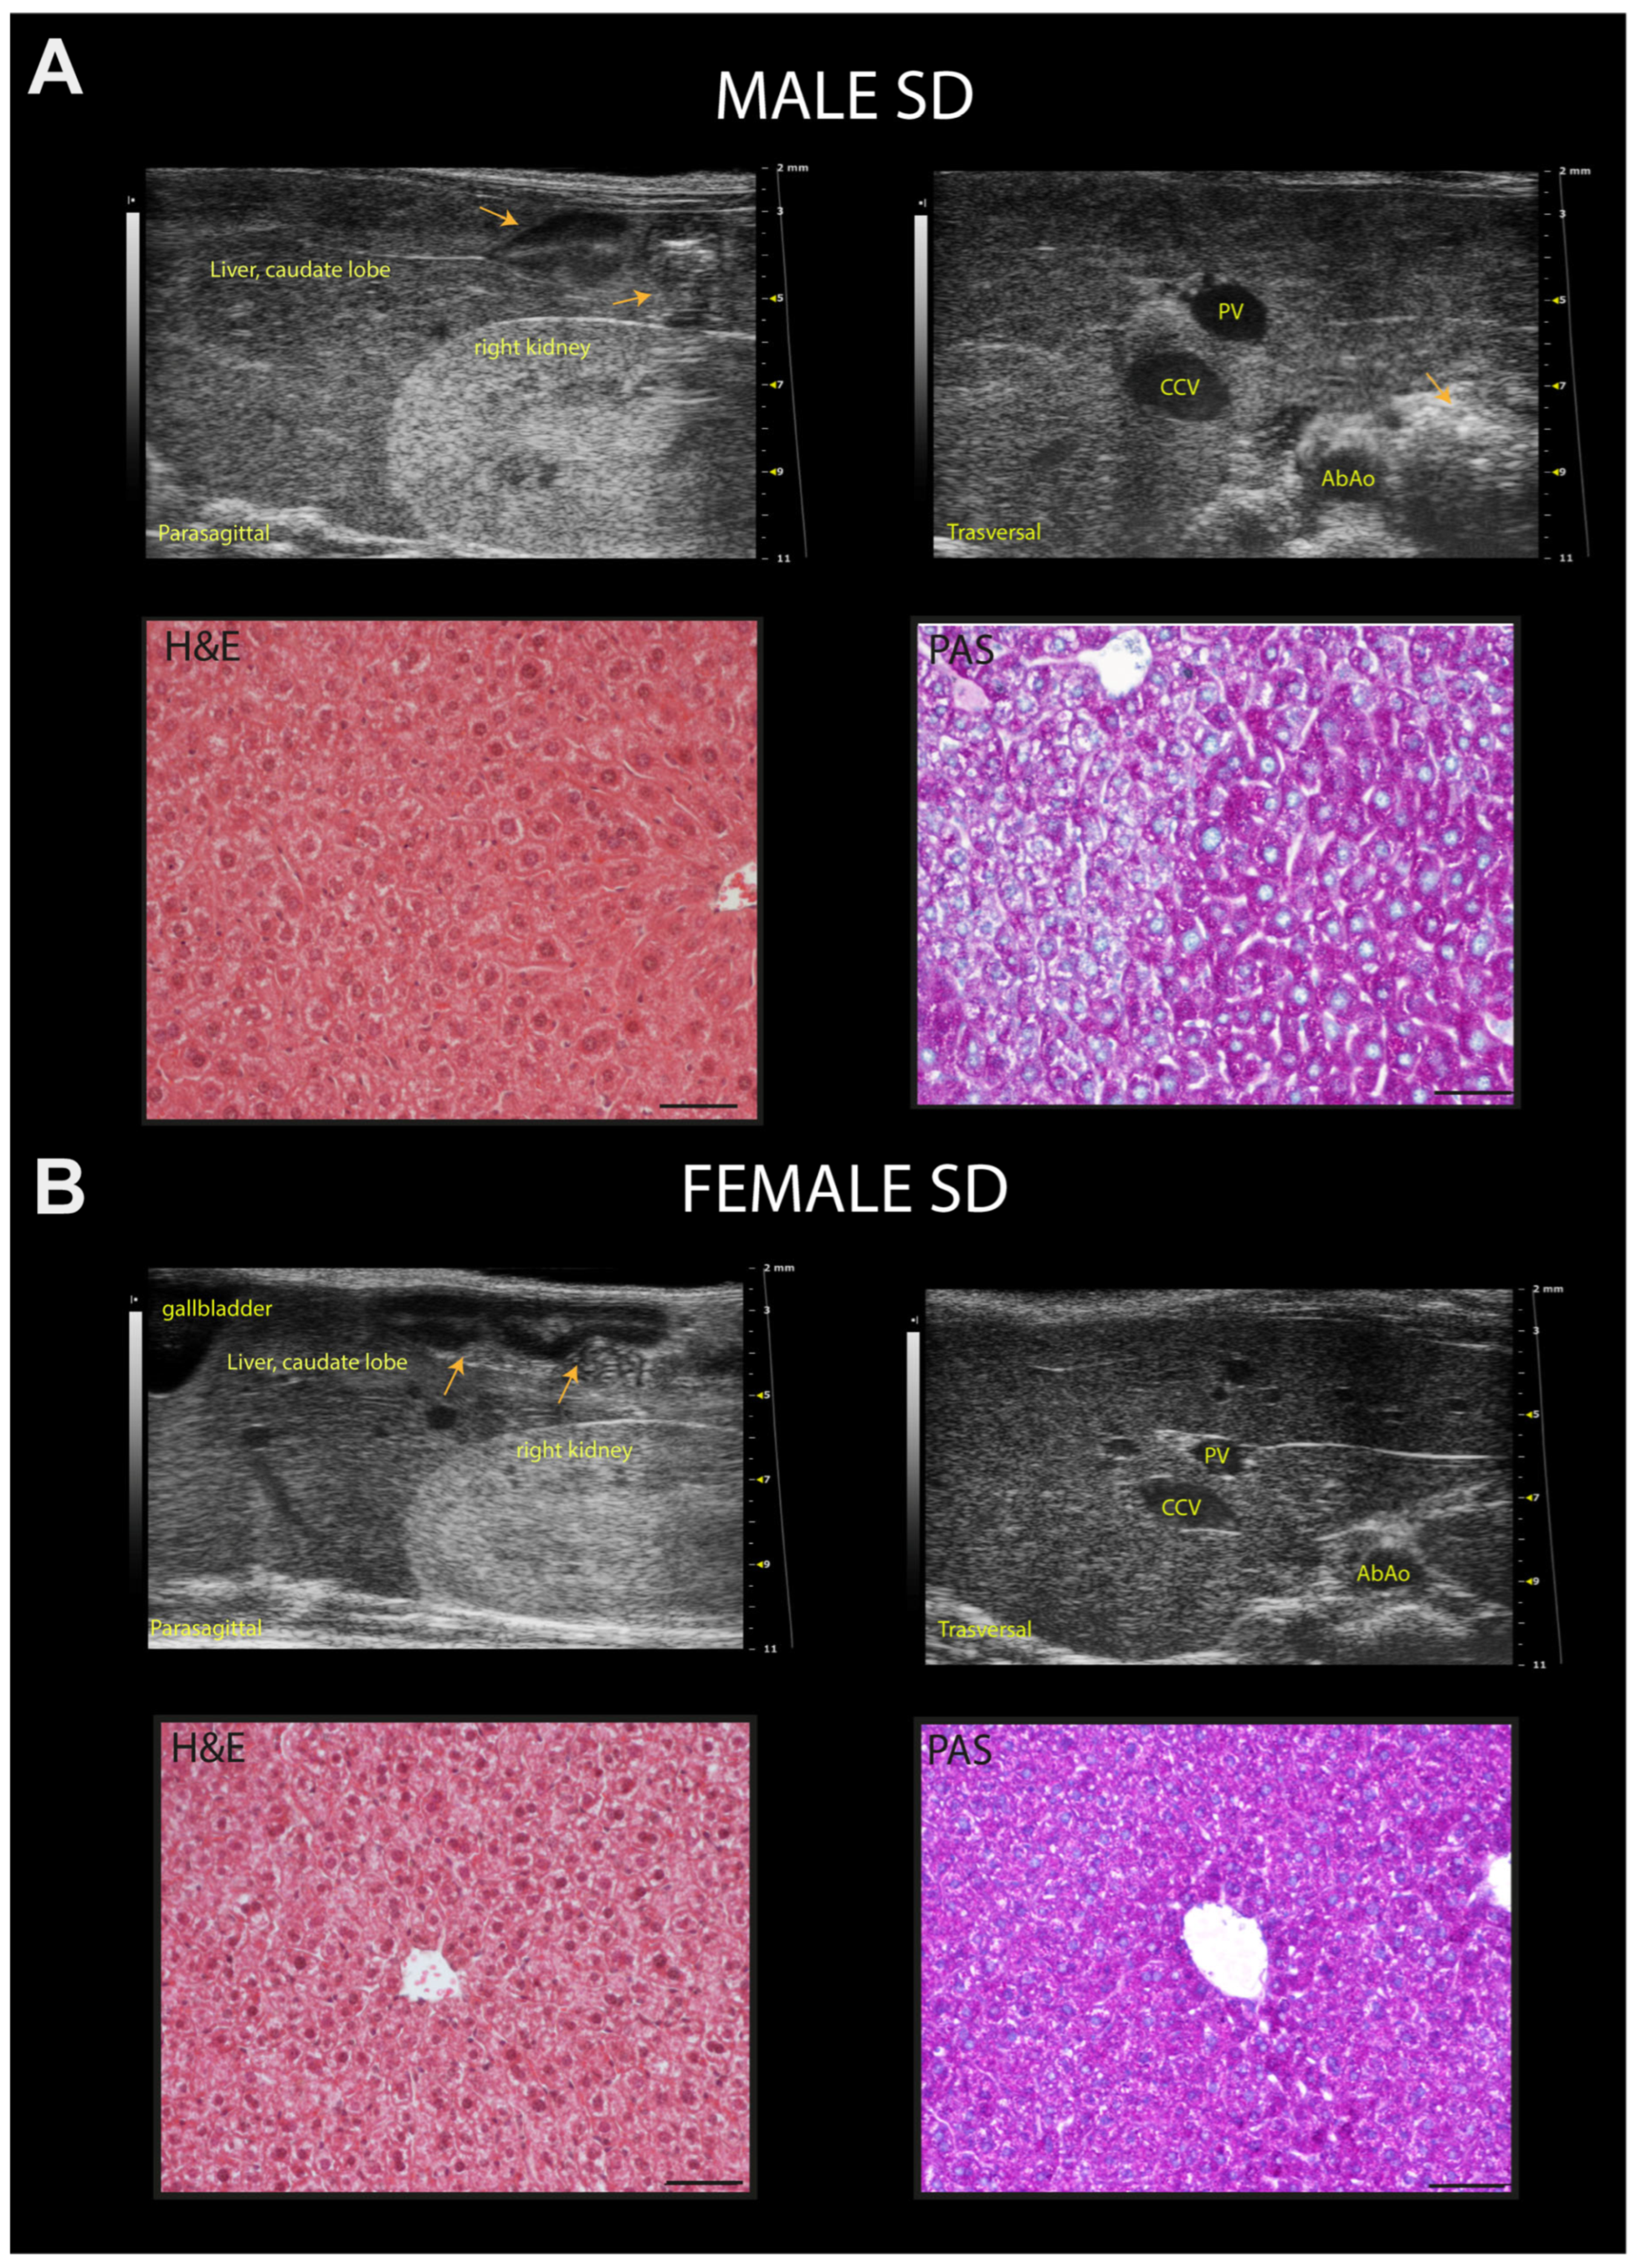

3.6. WD Causes Progressive Structural and Functional Changes in the Heart, Liver, and Kidney of C57Bl/6J Mice That Can Be Detected Early and Monitored In Vivo by HFUS

3.7. WD Induces Histological Changes in the Liver and Kidney of C57Bl/6J Mice